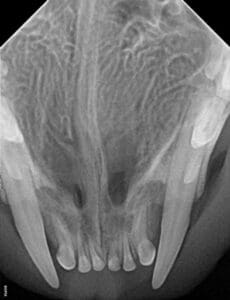

Even though this cat was young, the lower canines had already caused severe bone loss by putting pressure on the tissue around the upper canines, as seen in the following dental radiograph.